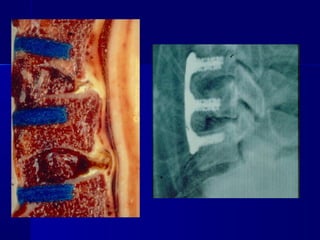

AAnntteerriioorr PPrroocceedduurree

Anterior – Posterior decompression aanndd ssttaabbiilliizzaattiioonn

IIMMPPLLAANNTTSS

IImmppllaannttss ffoorr

AAnntteerriioorr

CCoorrrreeccttiioonn

aanndd

SSttaabbiilliizzaattiioonn

ffoorr

PPoosstteerriioorr

AAnntteerriioorr --

CCoorrrreeccttiioonn aanndd